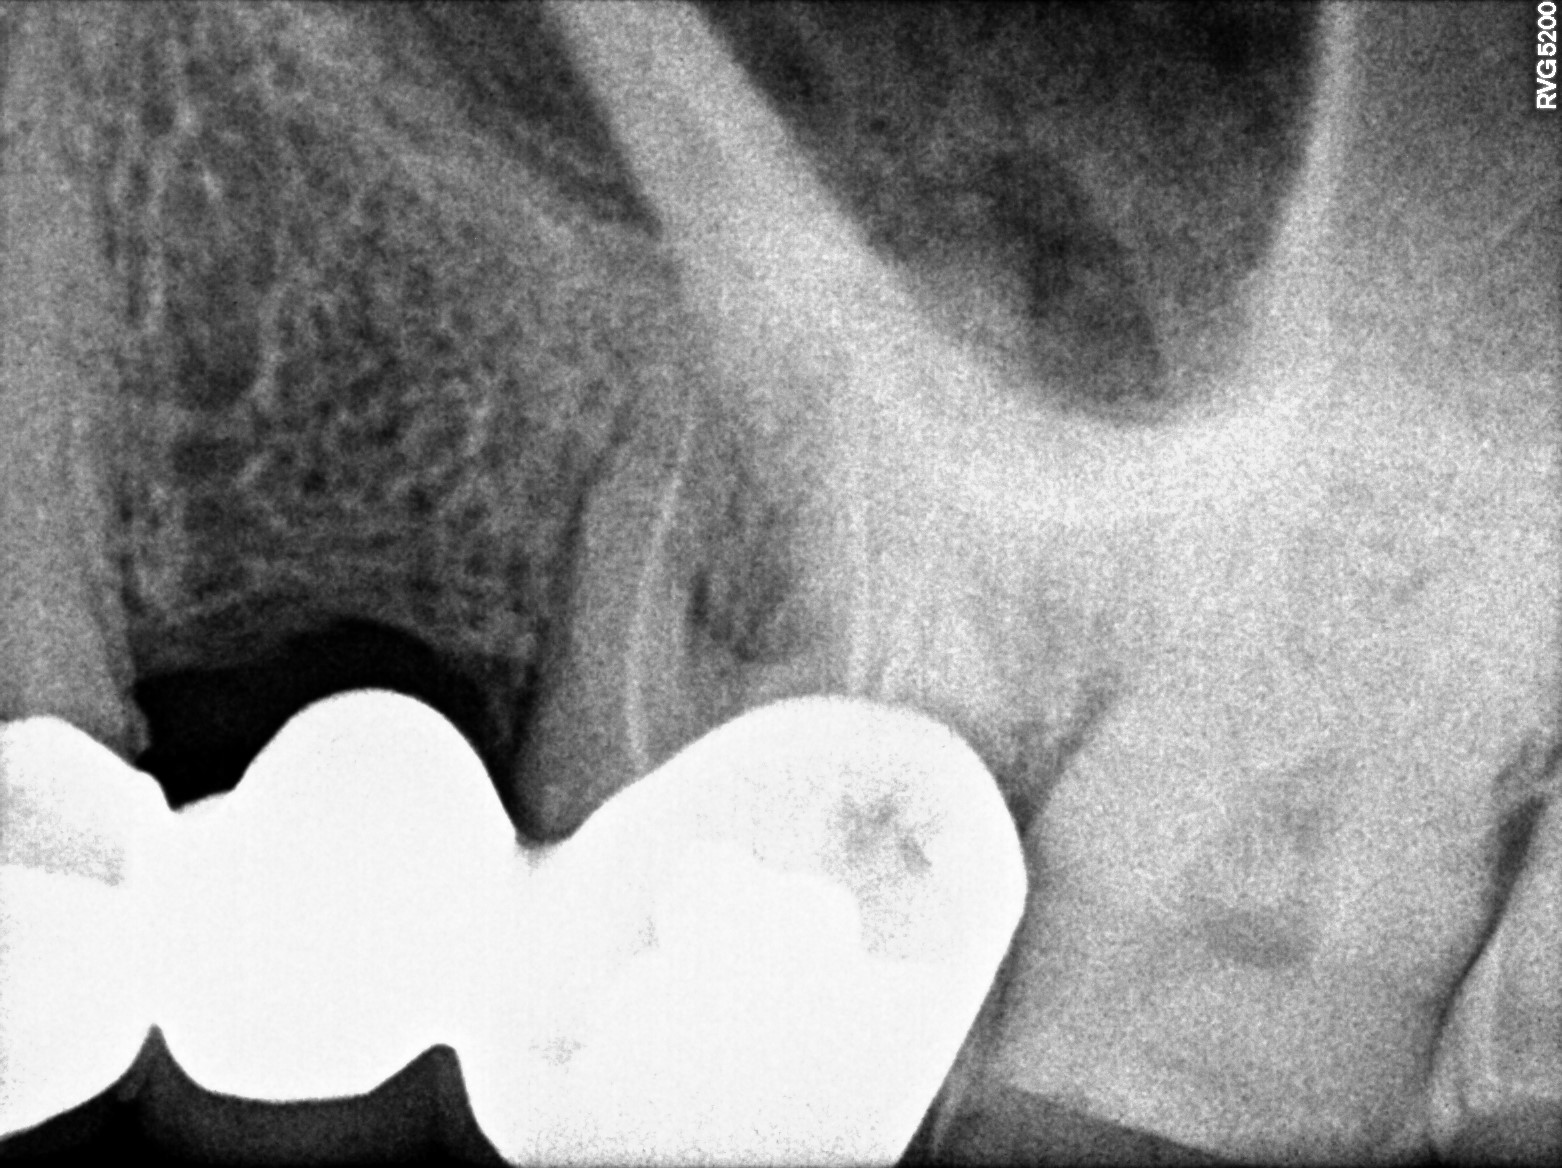

Dental Radiographs FHIR: DocumentReference · LOINC 24641-7

xray_1773475755_1.jpg

24641-7